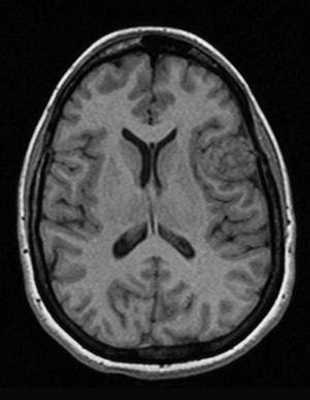

Классический пример МРТ снимков головного мозга показан на рисунках ниже. Магнитно-резонансная томография выполняется в поперечной (или аксиальной - рисунок снизу) и продольной (или сагиттальной — рисунок сверху) плоскостях.

Исследование выполняется в нескольких режимах. Основные из них Т1 и Т2. Изображения, полученные в данных режимах, часто также называют Т1-взвешенными или Т2-взвешенными снимками. Изображения, показанные выше, сделаны в Т1-режиме.

Главное отличие этих режимов - в том, как на снимках отображается жидкость и воздух. В Т1 режиме ткани, содержащие большое количество воды, имеют более темную окраску, в то время как в Т2 режиме они яркие, светлые. Это легко понять, посмотрев на снимки выше - глазные яблоки визуализируются в виде светлых парных округлых образований с одной стороны яркие и светлые, с другой - темные. Следовательно, снимок справа сделан в Т1 режиме, снимок слева - в Т2. Также существует разница в том, как в этих режимах отображается серое вещество головного мозга. В Т2 режиме оно светлее, чем белое вещество.

Как же узнать, есть ли на снимках признаки болезни? Самое главное - запомнить, как выглядит головной мозг здорового человека. Врач, изучая снимки пациентов, постоянно сравнивает их с нормальными снимками, хранящимися у него в голове. Чтобы понять, как это происходит - посмотрите на снимки внизу:

Перед вами - два снимка, сделанных в одном режиме. Снимок снизу - норма. Какое заболевание, в таком случае, есть на верхнем снимке? Чтобы понять это, нужно сравнить эти изображения. Явно видно отличие - на верхнем снимке в правой части головного мозга есть новообразование. Разница еще заметнее, если сравнить левую и правую части того же снимка.